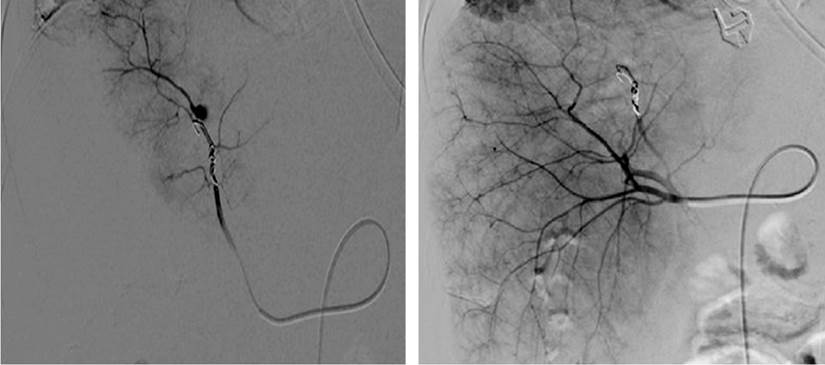

The aneurysm was then embolized (Figure 2), and the patient evolved favorably without further episodes of digestive bleeding and with complete resolution of the biliary obstruction.

Our final diagnosis was an upper gastrointestinal hemorrhage caused by the rupture of an aneurysm of a segmental branch of the right hepatic artery.